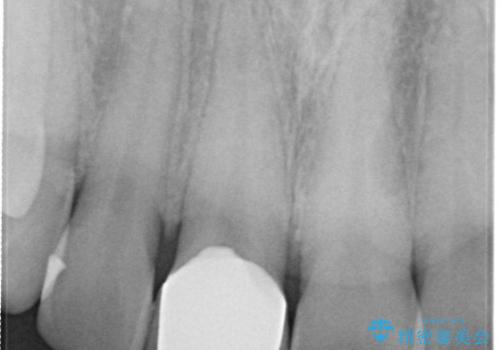

- 前歯の歯並びが気になるとのことで来院されました。

右上の1番目の歯が内側に入り込んでしまっており、その歯がの先端がすり減ってしまっていました。

インビザラインによる矯正治療で前歯の歯並びを改善し、セラミッククラウン装着により歯の形態の回復をする計画としました。